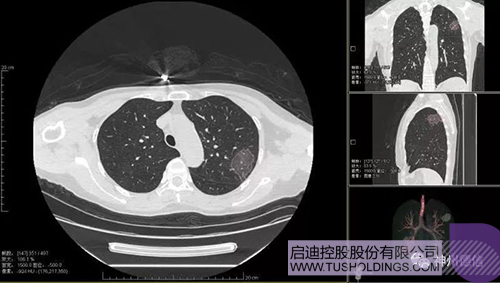

神州德信新冠肺炎檢測及智能量化分析系統

啟迪戰(zhàn)略投資企業(yè)神州德信作為國內領先的肺部影像人工智能企業(yè)�,針對新型冠狀病毒肺炎開發(fā)了智能檢測及量化分析系統,并在陜西�、重慶等地定點醫(yī)院投入使用。該系統在疑似病例大規(guī)?���?焖俸Y查及精準診斷方面發(fā)揮了重要作用,特別是其具有的肺炎患者臨床影像跟蹤量化隨訪功能��,為快速有效阻斷疫情擴散提供了有力武器����。